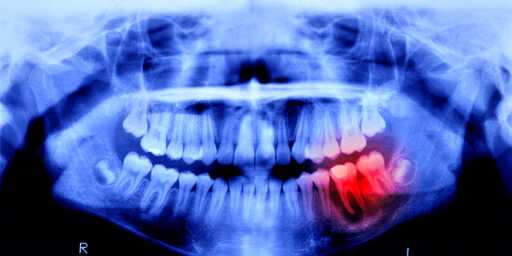

I’ve seen one of these talked about before, and the mechanism seemed to be in that one that there’s a gene in our DNA that triggers us to grow new teeth (that’s how we replace our baby teeth with adult teeth), but that that gene turns off after we grow in our set of adult teeth. It’s apparently the same gene that allows sharks to grow new teeth. What the drug does is it turns that gene back on, allowing us to grow new teeth to replace lost ones.

This might not be the same study though, as I’ve also seen one previously years ago that was about a drug that turned on a gene in our teeth to allow them to repair the enamel in them and fill in cavities by putting biodegradable gauze soaked in the drug inside a cavity and letting the tooth do the rest.